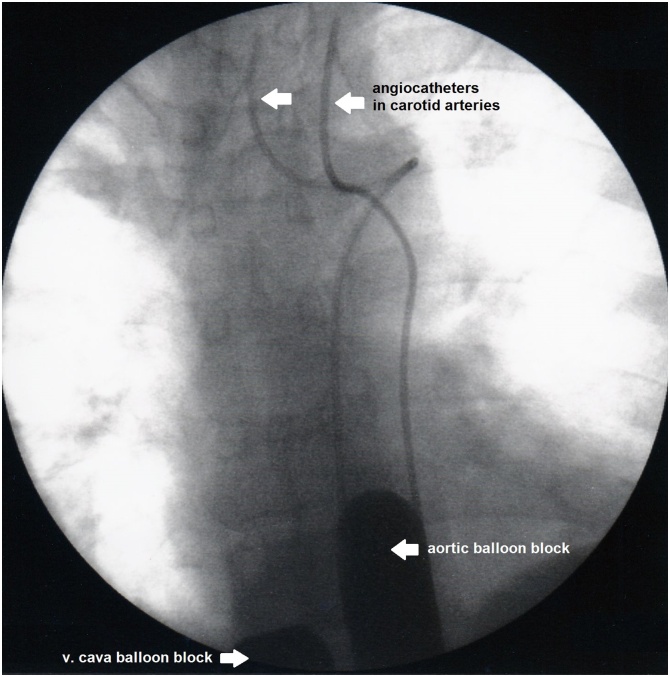

In the first isolated thoracic perfusion (Fig. 1) on 7th December 2010 the chemotherapeutic agents were administered via two angiographically placed common carotid artery catheters (Fig. 2) at a dosage of totally 100 mg cisplatin, 60 mg adriamycin and 20 mg mitomycin followed by chemofiltration in order to reduce systemic toxicity. After a 15 min short-term carotid artery infusion of this three-drug combination into the isolated perfusion circuit, followed by 45 min of chemofiltration, the patient did not suffer any systemic toxicity and reported 14 days thereafter a substantial improvement of his voice and disappearance of the previously palpable lymphnode metastasis on the right side of the neck.

Fig. 1.

Scheme of isolated thoracic perfusion. Aorta and vena cava are balloon blocked at the level of the diaphragm. Both upper arms are blocked with pneumatic cuffs. Chemotherapy is administered over 15 min via implanted or angiographic carotid artery catheters. After 15 min all blocks are released and chemofiltration for elimination of residual drugs is started.

Fig. 2.

Intraoperative contrast imaging of two angiographic carotid artery catheters and balloon blocked aorta and vena cava.